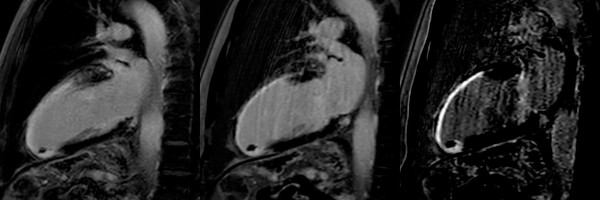

MR Cardio Narbendarstellung (PSIR Black Blood)

Der Kontrast zwischen Narbe und Blood pool (mit Kontrast angereichertes Blut im linken Ventrikel) ist in der konventionellen T1 IR TFE, wie auch in der PSIR Sequenz suboptimal. Speziell Sub-endocardiale Infarkte sind sehr schwer zu detektieren oder abzugrenzen.

Erst eine PSIR Black-Blood vermag den Infarkt sehr schön zu differenzieren